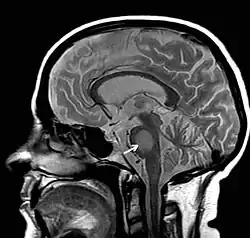

Die Zentrale pontine Myelinolyse (ZPM) (lat. pons, Brücke, pontine die Brücke betreffend; griech. μῦελόν, myelon, Mark, λύσις, lýsis, Auflösung) ist eine neurologische Erkrankung, bei der es zu einer Schädigung der Umhüllung von Nervenfasern besonders im Pons (Hirnstamm) kommt. Sie wird durch zu schnelle Korrektur eines krankhaft verminderten Natriumspiegels (Hyponatriämie) im Organismus hervorgerufen.

Zentrale pontine Myelinolyse, MRT-Bild des Gehirns axial in FLAIR-Wichtung; krankhaft ist der helle Ring in der Bild-Mitte